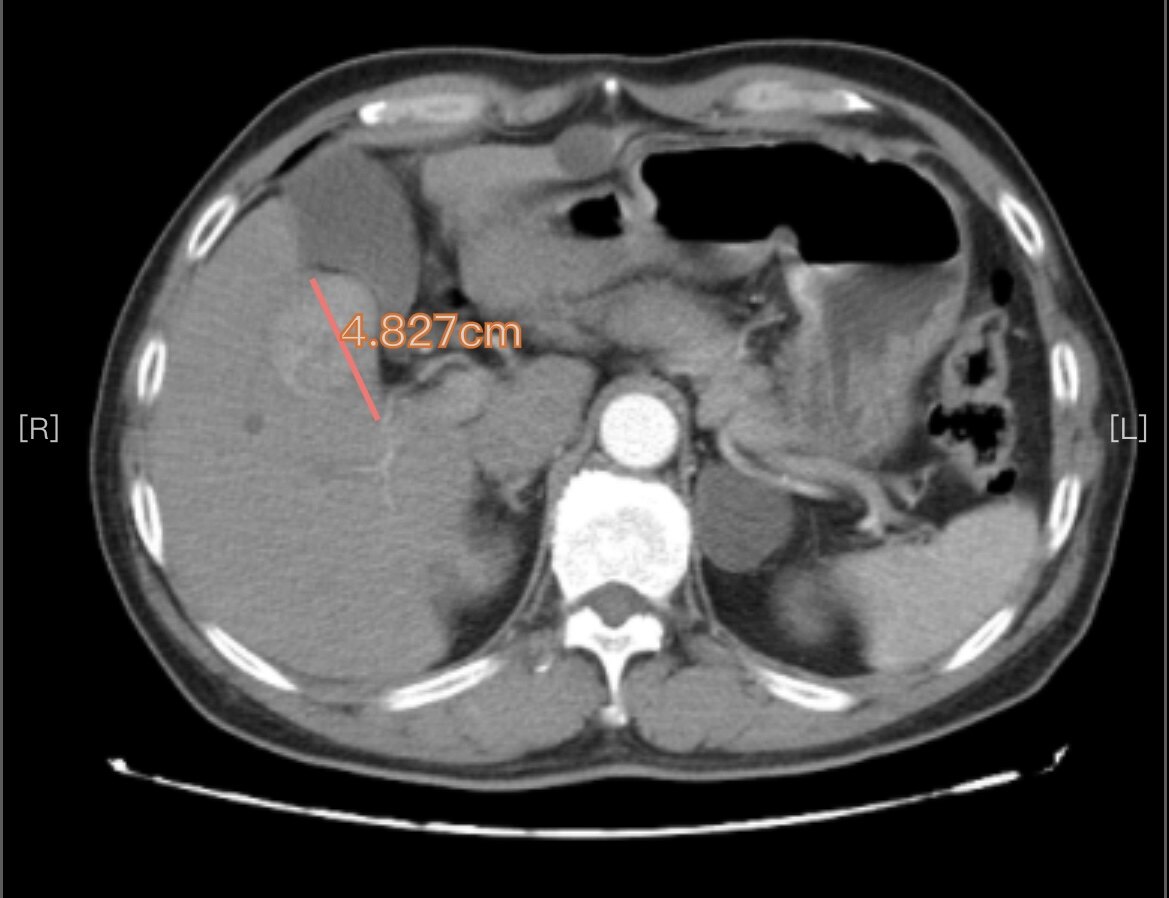

手术切除是早期肝癌安全(手术死亡率为0)、有效(5年生存率达到70%)、高性价比(报销前费用在3万元左右)的治疗方式。以下4例有乙肝病史,经定期筛查(肝脏B超和甲胎蛋白)发现的早期肝癌,手术切除后平均住院时间6天,无任何并发症,自费仅数千元。